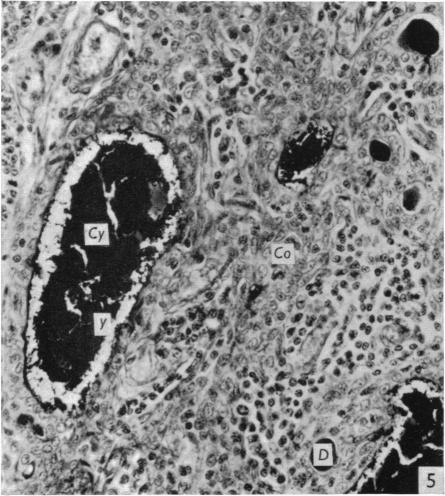

The effect of castration, oestrogens, testosterone and the oestrous cycle on the cortical epithelium of the thymus in male and female rats.

J Anat. 1968 Jun;103(Pt 1):113-33.